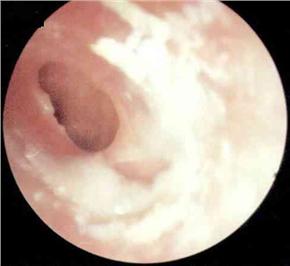

中耳炎病理图

慢性中耳炎按患病时间、病情轻重不同分为三种:单纯性,脓疡性和胆脂瘤性。它们共同的表现是均有耳流脓,反复不止,有时脓液中还混有血性分泌物;另外,有耳鸣及听力下降,如果出现并发症,会有眩晕和头痛。